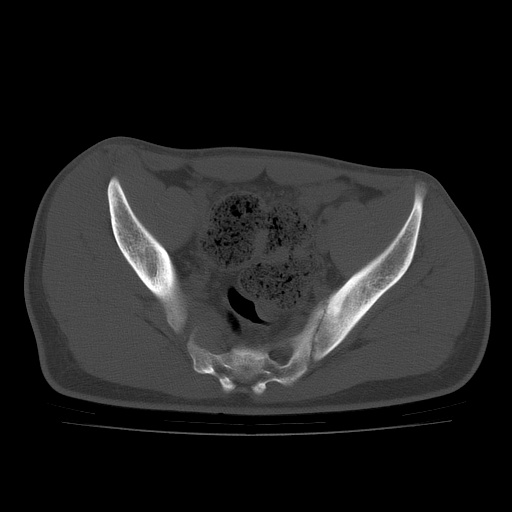

患者男性,18岁 腰腿痛1年  骶髂关节改变本人考虑强直性脊柱炎。

两侧骶髂关节骨质破坏,关节面毛糙,符合强直性脊柱炎骶髂关节改变。

符合强直性脊柱炎,虫蚀样骨质破坏。

两侧骶髂关节骨质破坏,关节面呈锯齿样改变关节间隙变窄,考虑强真性脊柱炎

双侧骶髂关节关节间隙变窄,边缘毛糙,关节面硬化,可见囊变!符合强直变现!

两侧骶髂关节骨质破坏以髂骨为主,间隙变窄,强直性脊柱炎